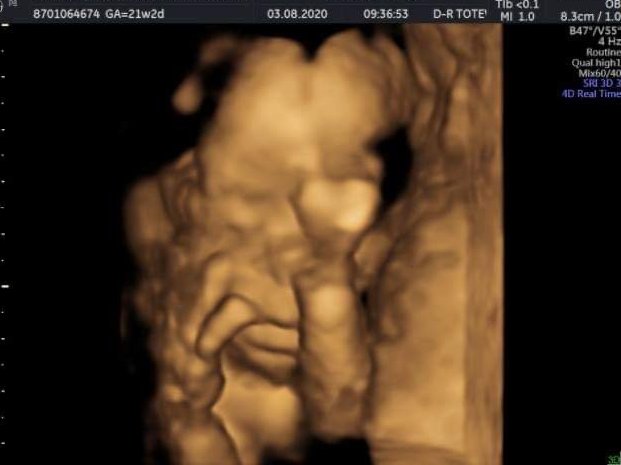

Здравейте , момичета . Не съм писала скоро , но си ви чета редовно . Аз днес бях на втора фетална - 21+2 г.с. Малчо е добре, доктора каза , че всичко изглежда чудесно . 420 гр. , голям мъж 💙 Ръцете му бяха постоянно пред лицето и едва го хванахме . Плацентата се е вдигнала , шийката е чудесна , май беше 4.2 см. Прилагам снимка на малката муцунка ☺